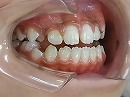

治療中ですが、治療前に比べると開咬が改善してきています。

オープンバイト治療中